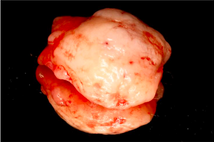

Before Treatment